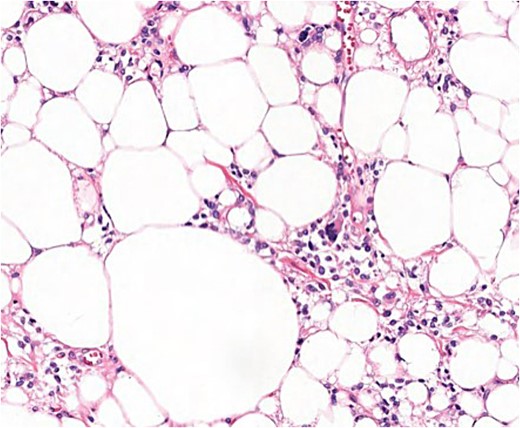

After the final diagnosis, surgery was scheduled in an ambulatory regime. Surgical excision of the tumour was performed generating a skin area defect on the left shoulder covered with a skin graft from the lateral aspect of the left thigh of the patient. The surgical piece presented lipomatous macroscopic characteristics with a total weight of 3110 g (Fig. 5). Under the microscope, floret-like spindle cells are presented, embedded together with mature adipocytes (Fig. 6).

Microscopic findings (H & E ×40): well-circumscribed lesion at the profound dermis, composed of mature adipocytes, with occasional pleomorphic lipoblasts and spindle cells in the stroma some of which presented ‘floret’-like morphology; focal areas of necrosis and absence of mitotic activity; intense and diffuse response to CD34.